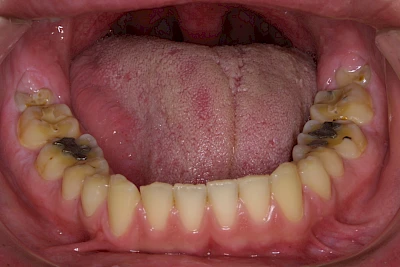

Auswaschung (Erosion) dagegen ist eine Verschleißerscheinung der Zähne aufgrund von immer wiederkehrenden Säureangriffen durch die Nahrung, verstärkt zum Beispiel durch den Genuss säurehaltiger Getränke oder Speisen. Auch bei Menschen mit einer Essstörung (z. B. Bulimie) können die Zähne durch die Magensäure ausgewaschen erscheinen.

Eine Sonderform sind sogenannte keilförmige Defekte im Bereich der Zahnhälse. Hier geht man davon aus, dass Knirschen und Pressen in Kombination mit falschen Putzgewohnheiten (zu hoher Putzdruck, Verwendung von Zahnpasta mit hohen Abrasionswerten) eine Rolle spielen.